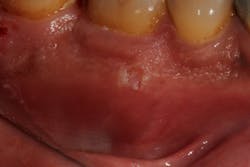

Figure 1: Minor aphthous ulcer

- 80% of canker sores are minor aphthous ulcers. These appear as round white lesions 2 mm to 8 mm in size, surrounded by a thin red halo usually occurring on nonkeratinized oral mucosa with a duration time of 10 to 14 days (figure 1).